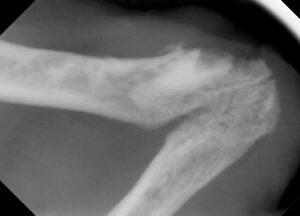

レントゲン検査では、

右上顎臼歯の残根2本と下顎臼歯の残根1本、犬歯は歯冠切除を実施していましたが歯肉に近い場所でした。